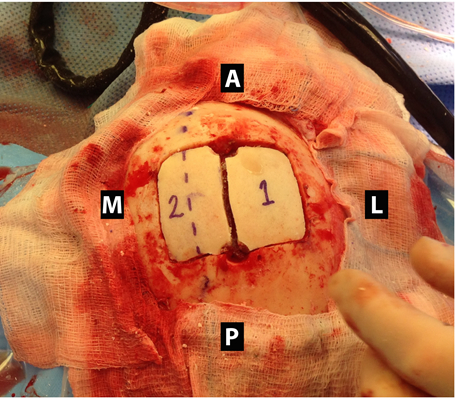

顱內血腫圖片

硬膜下血腫 (7)

硬膜下血腫 (8)

硬膜下血腫 (9)